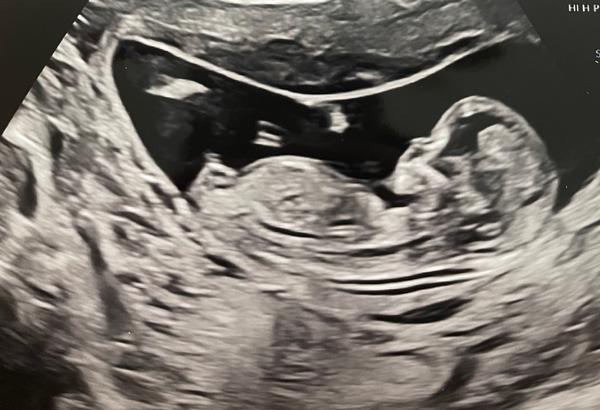

chtěla bych se zeptat, zda-li byste odhadl pohlaví miminka z fotek, které jsou z prvního screeningu ve 13. tt.

z fotografie to jednoznačné není. Jednak je spolehlivost odhadu ve 13. týdnu malá a také statický snímek nedokáže nahradit vyšetření v reálném čase.